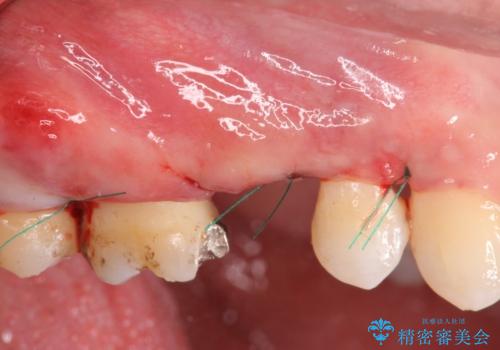

また噛み合わせが深くブリッジの強度が十分に確保できないことから、抜歯時に歯周外科を行うことで十分に安定したクラウン装着をできるような処置を行っています。

術前・術後でブリッジ治療をした部分の歯肉ラインを整えたことで安定したブリッジを製作することができました。